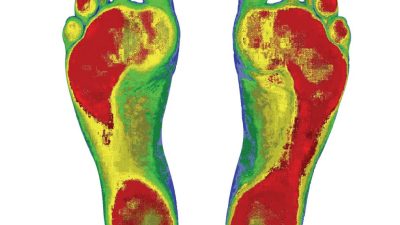

Dijital Ayak Analizi (Pedobarografi)

İlk aşamada kişi özel sensörlü basınç platformuna çıkar. Bu sistem sayesinde:

• Ayak basınç dağılımı

• Yük merkezi

• Denge analizi

• Statik ve dinamik basış farkı

• Yürüyüş paterni

ölçülür. Elde edilen veriler bilgisayar ortamında detaylı şekilde raporlanır.